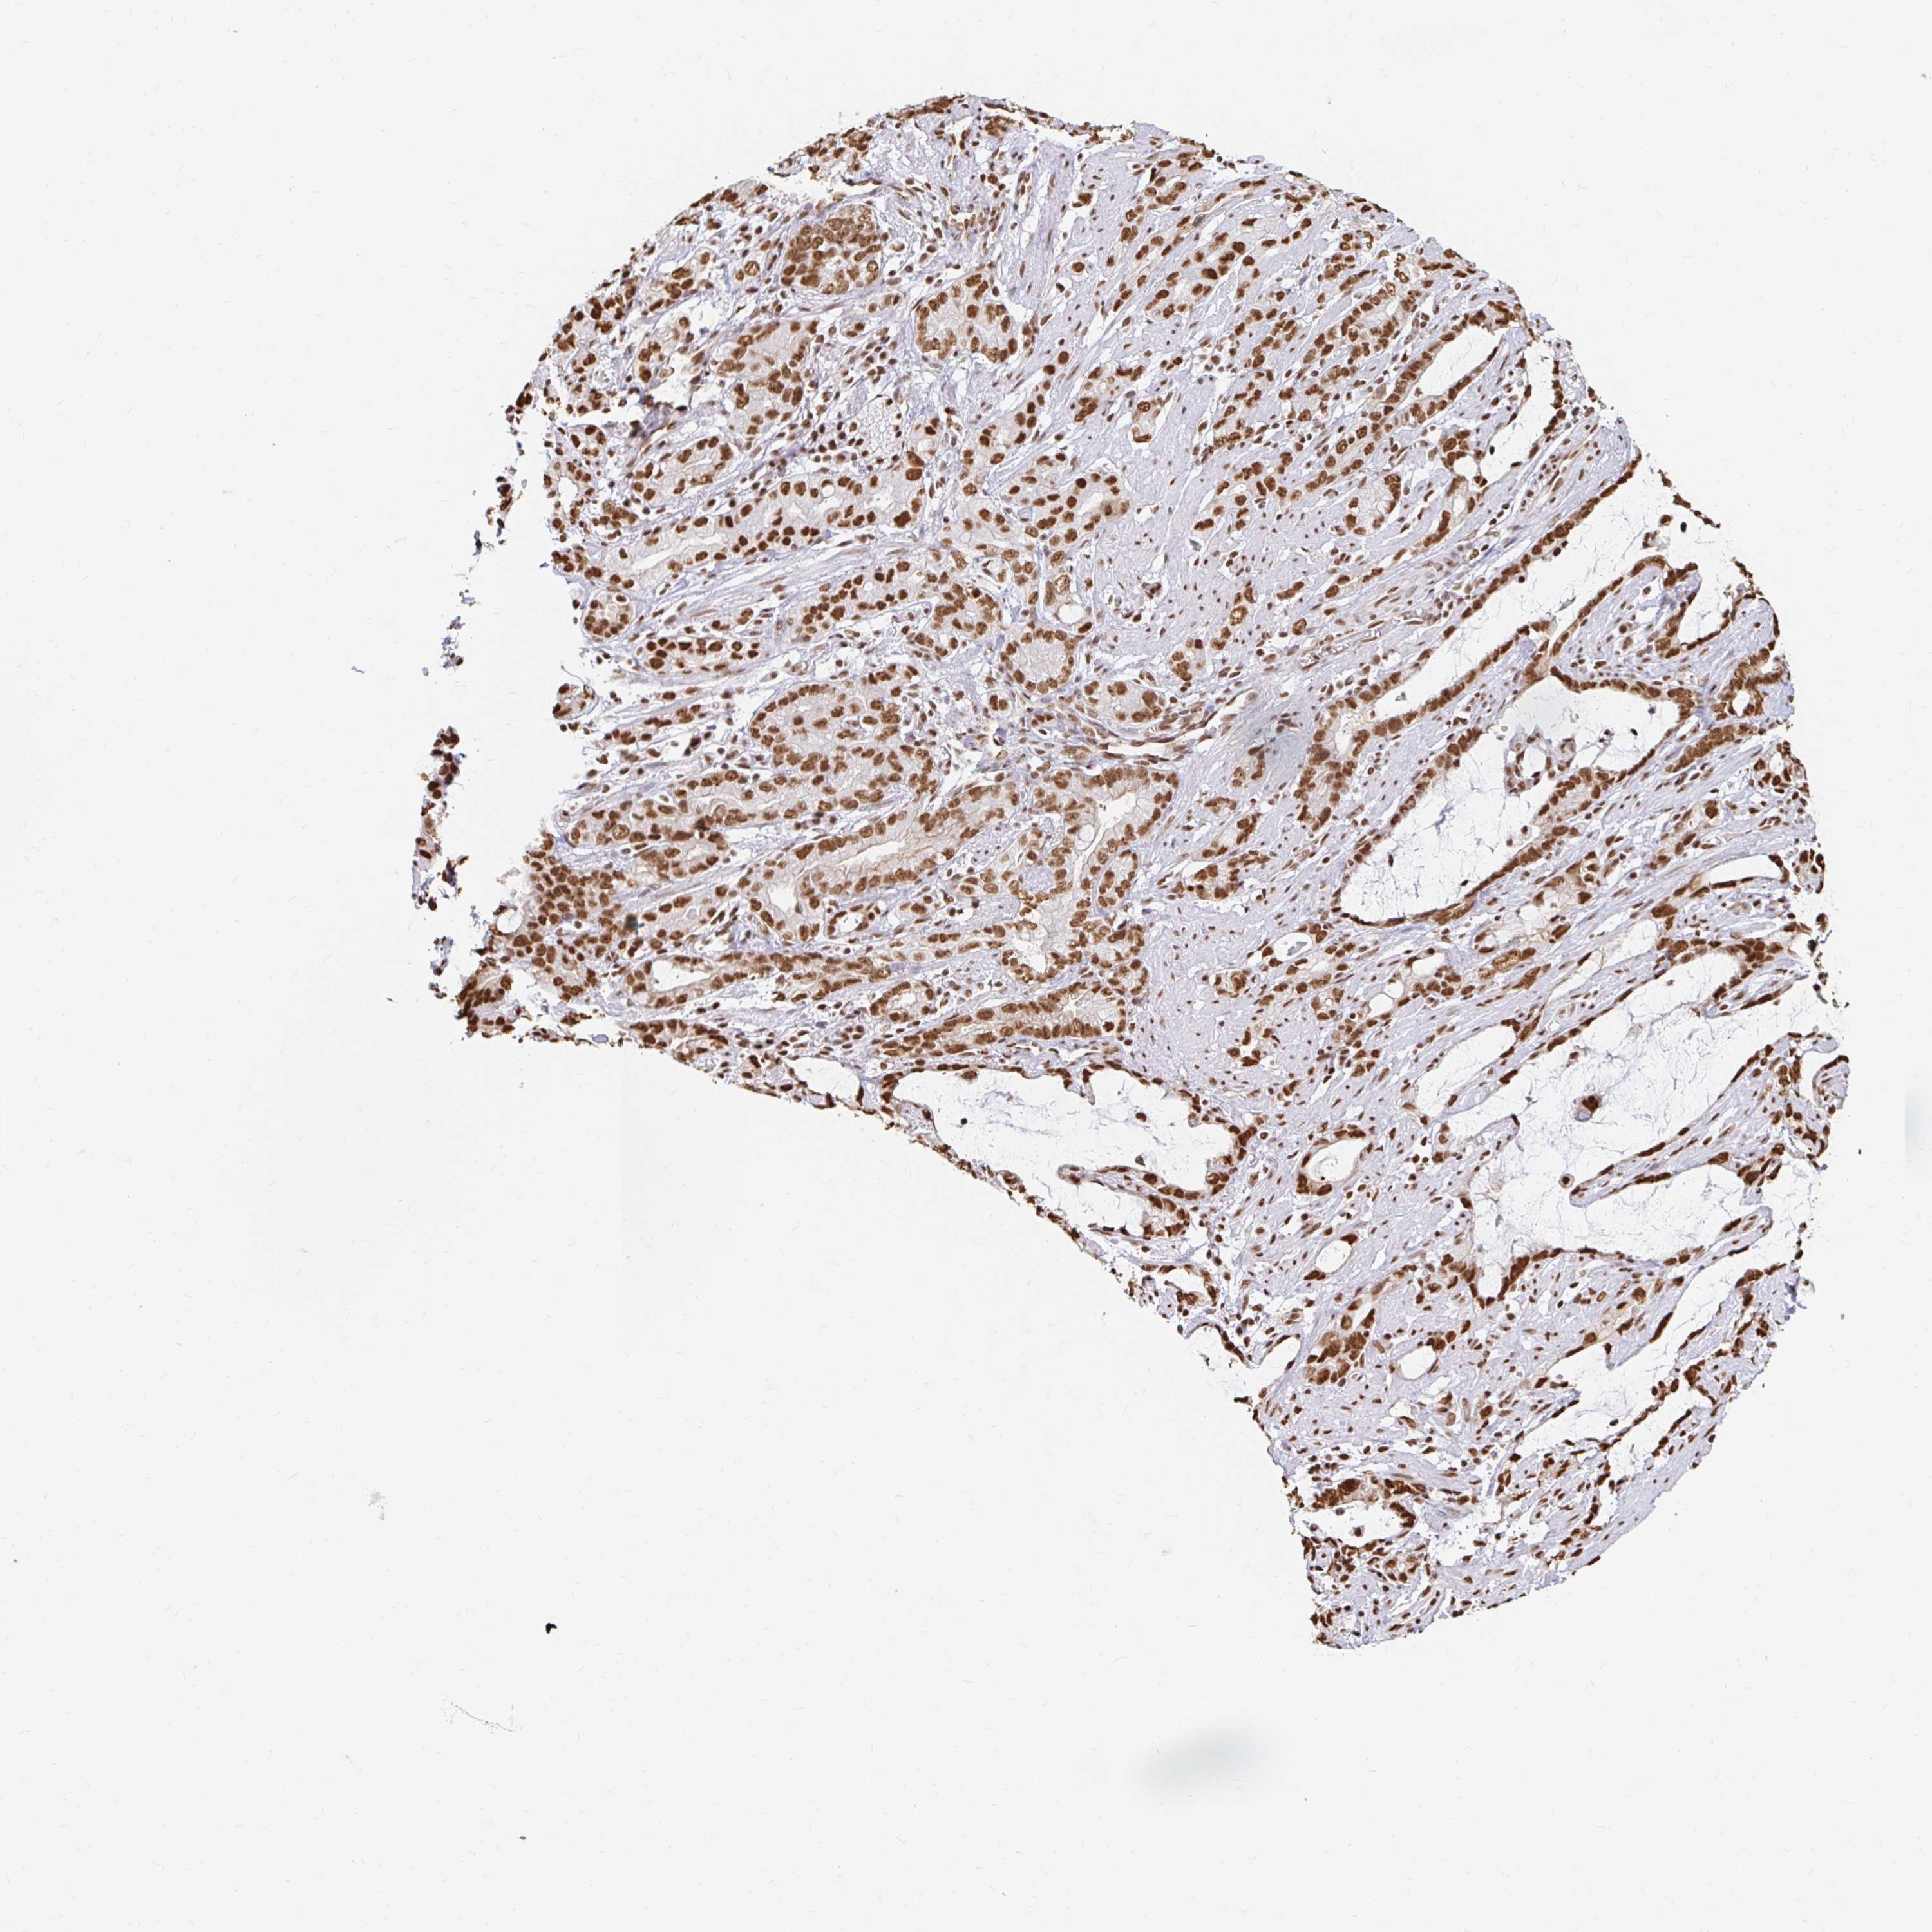

STOMACH CANCER - Protein expressioni

A mouse-over function shows sample information and annotation data. Click on an image to view it in a full screen mode. Samples can be filtered based on level of antibody staining by selecting one or several of the following categories: high, medium, low and not detected. The assay and annotation is described here.

Note that samples used for immunohistochemistry by the Human Protein Atlas do not correspond to samples in the TCGA dataset.

Antibody stainingi

Antibody staining in the annotated cell types in the current human tissue is reported as not detected, low, medium, or high, based on conventional immunohistochemistry profiling in selected tissues. This score is based on the combination of the staining intensity and fraction of stained cells.

Each image is clickable and will lead to virtual microscopy that enables deeper exploration of all samples and also displays staining intensity scores, fraction scores and subcellular localization as well as patient and tissue information for each sample.

Antibody HPA041057

Antibody HPA058707

Antibody CAB011532

Staining

High

Medium

Low

Not detected

Intensity

Strong

Moderate

Weak

Negative

Quantity

>75%

75%-25%

<25%

None

Location

Nuclear

Cytoplasmic/membranous

Cytoplasmic/membranous,nuclear

Adenocarcinoma, NOS

Adenocarcinoma, High grade